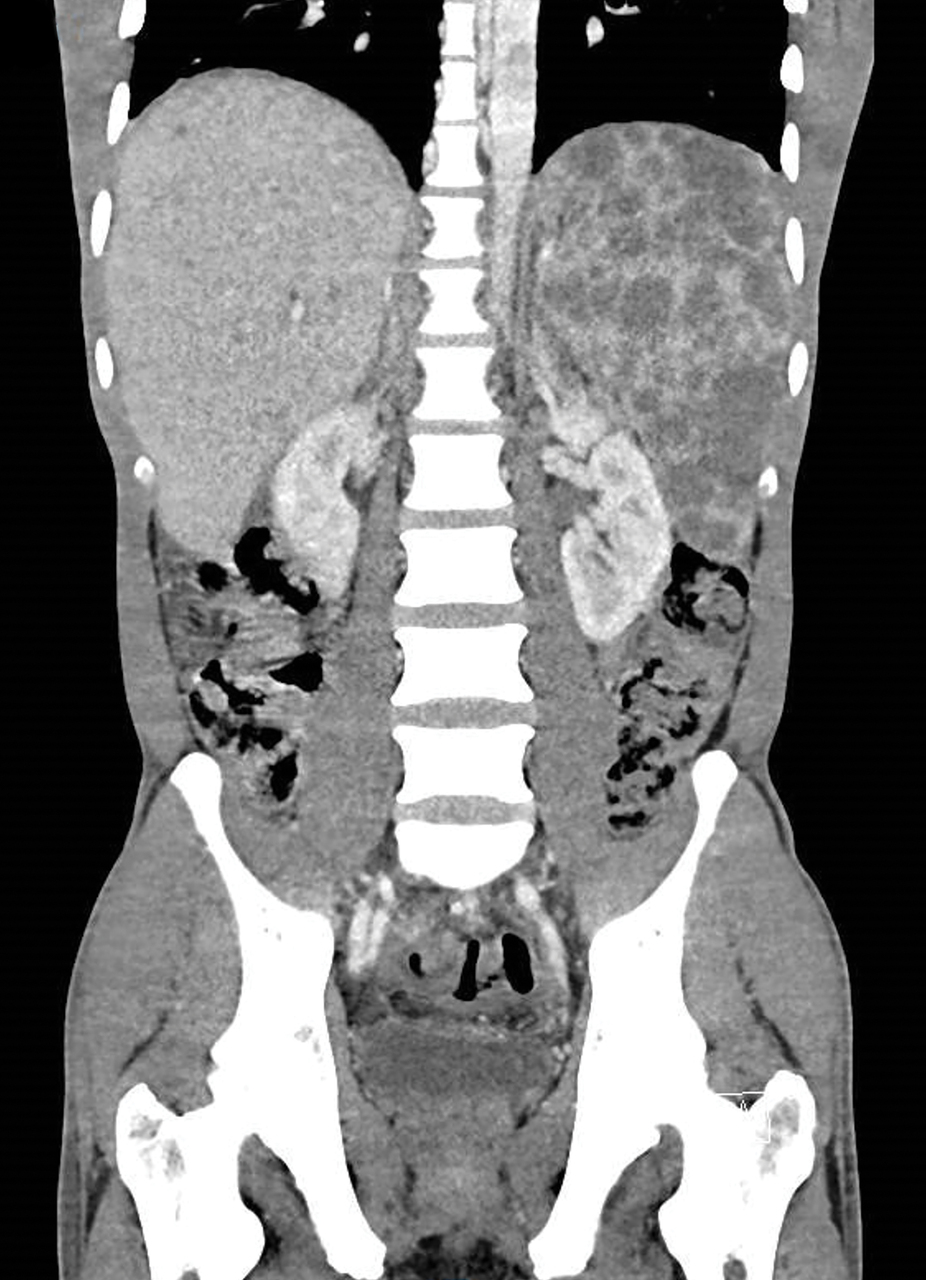

Homme de 34 ans consultant pour des douleurs abdominales, un amaigrissement de 10 kg, une fièvre à 39°C et une CRP de 69 mg/L.

Quel est votre diagnostic ?